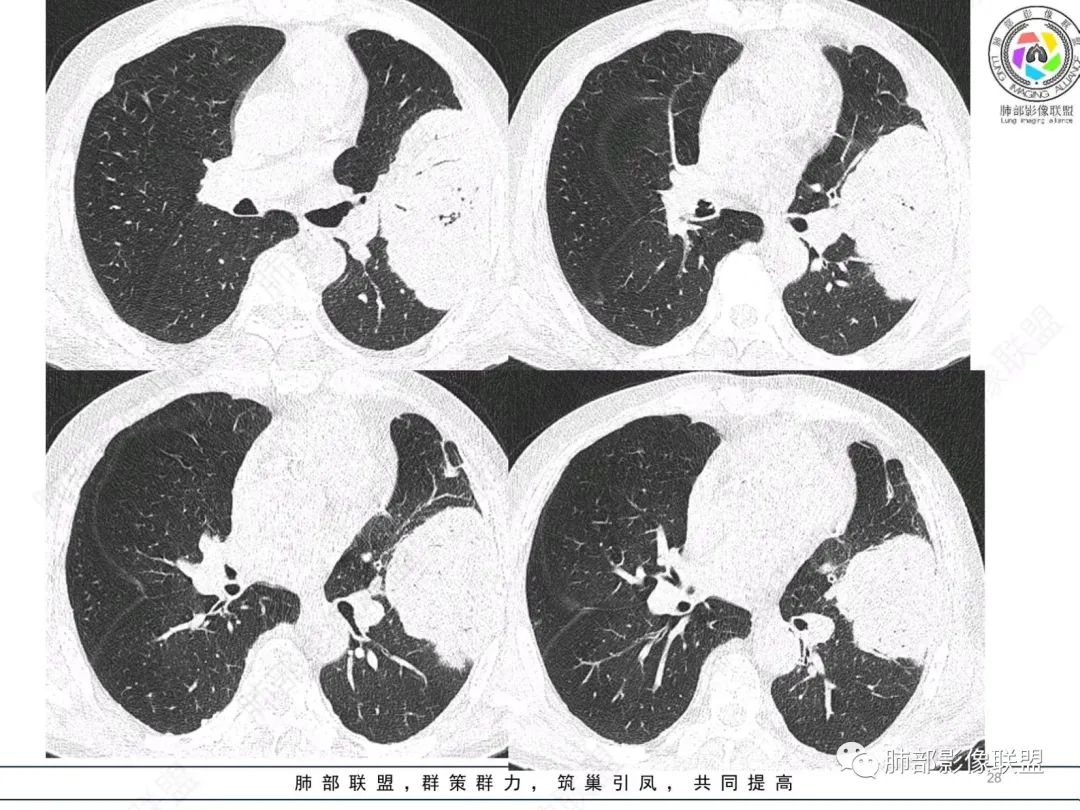

左肺上叶大肿块,膨胀性生长,边界清,密度较低,见部分坏死区,强化弱,肿块见支气管充气V扩张征,分布僵直,枯树枝特点,另一个重要特点血管造影征,淋巴瘤,肿块长轴与胸膜平行,与隐球菌鉴别,隐球荚膜抗原检查,明确诊断经皮肺穿刺。另胸膜钙化(问诊既往有无患胸膜炎病史)。

左肺上叶胸膜下肿块,宽基底与胸膜相连,跨叶裂,边缘清晰膨隆,其内支气管充气,部分扩张、僵直,无明显强化,血管造影征,考虑淋巴瘤,鉴别腺癌

左肺胸膜下巨大占位,跨叶裂,宽基底与胸膜相连,胸膜钙化,平扫密度较低,强化不明显,可见内部血管显影,支气管充气征和扩张,考虑为恶性,倾向于淋巴瘤

左肺上叶胸膜下肿块,膨胀性生长,边界清晰,密度不均部分坏死,未见强化,病灶内支气管迂曲扩张,病灶长轴与胸膜平行,胸膜下脂肪间隙存在,胸膜钙化,考虑放线菌?毛霉?鉴别淋巴瘤

左肺上叶肿块,宽基底与胸膜相连,跨叶裂,边缘清晰膨隆,可见小分叶,其内支气管充气,部分扩张、僵直,呈枯枝征,支气管达边征,增强无明显强化,可见血管造影征,考虑恶性病变,淋巴瘤,鉴别粘液腺癌。

我再建一下血管。支气管进入,但是近端推移,堵塞

大肿块,边缘光滑,深分叶

近端支气管堵塞、推移为主

部分类似于脐凹征

内部支气管扩张

肺动脉推移为主,边缘部分进入

大肿块、表面光滑但深分叶,肺门侧支气管堵塞

回头看,内部支气管近端其实不连续,伴随肺动脉不存在

4)密度:肿块平扫为软组织密度,由于体积较大,内部常见大片状坏死,可出现不规则厚壁空洞或坏死内多发无壁小空洞,坏死多不均匀:坏死灶内可见如柳絮样的斑片样强化灶,坏死边缘与非坏死区分界不清本例坏死较明显,密度不均匀。

5)肿瘤强化方式:肺部恶性肿瘤强化程度与其血供丰富程度相关,血供丰富多强化明显,反之则较差。由于PSC 周边实性部分富血供及内部黏液变性、坏死,增强后肿块多数呈轻-中度边缘环形强化或不均匀小斑片状强化。国外学者对照病理发现肿瘤细胞或胶原组织增强扫描时强化,无强化的低密度区代表了黏液样变性区和出血坏死区。